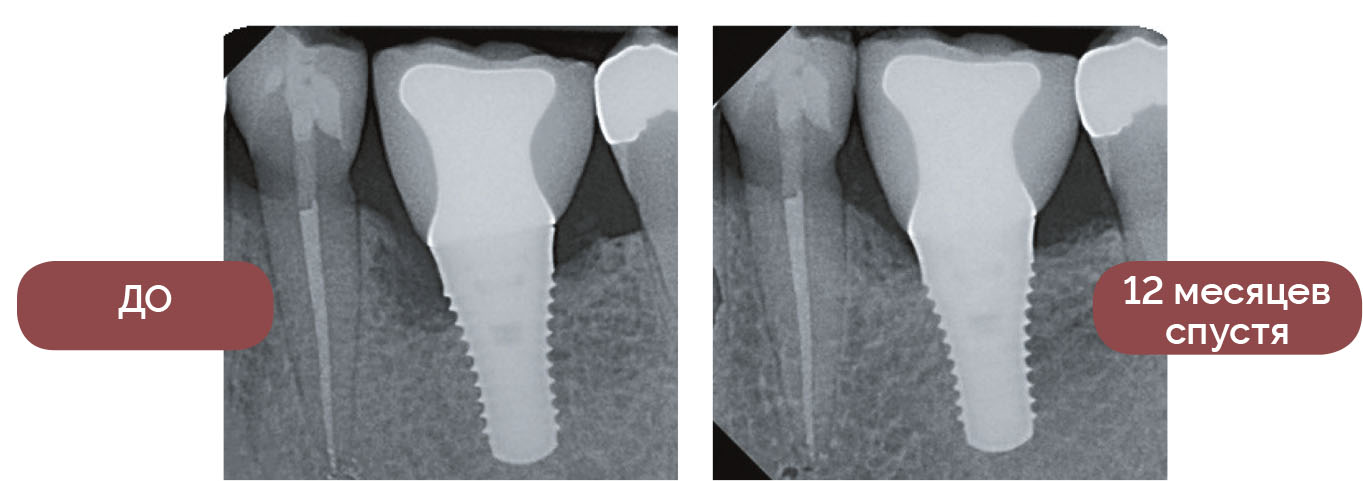

ЛЕЧЕНИЕ ПЕРИИМПЛАНТИТА

— Waterlase — неотъемлемая часть моей практики. Почти каждый день я стараюсь спасти имплантат с признаками отторжения, вылечить зуб с пародонтальной патологией, взять биопсию образования или устранить дефекты мягких тканей. Я не могу представить свою работу без Waterlase и настоятельно рекомендую каждому стоматологу пользоваться этим инструментом. Ваши пациенты будут благодарны.